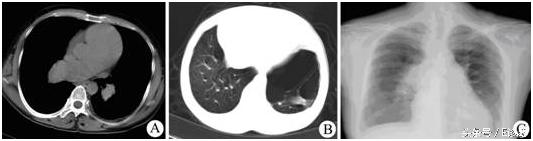

ec诊断,ecu诊断 胸部CT平扫纵隔窗(图A)、肺窗(图B);胸部正位平片(图C)

【影像表现】 胸部CT平扫纵隔窗(图A)可见肺动脉主干及左右肺动脉主支明显增粗,肺窗(图B)示胸廓前后径增大,双肺透光度增加,肺纹理牵拉稀疏,并可见左下肺肺大泡形成。胸部正位X平片(图C)可见肺动脉段突出,右下肺动脉干明显增粗直径大于14 mm,周围肺野肺纹理稍稀疏,形成“残根征”。左心缘下段圆隆上翘。

【诊断】 慢性肺源性心脏病(根据患者多年慢支肺气肿的病史结合和CT片可确诊)